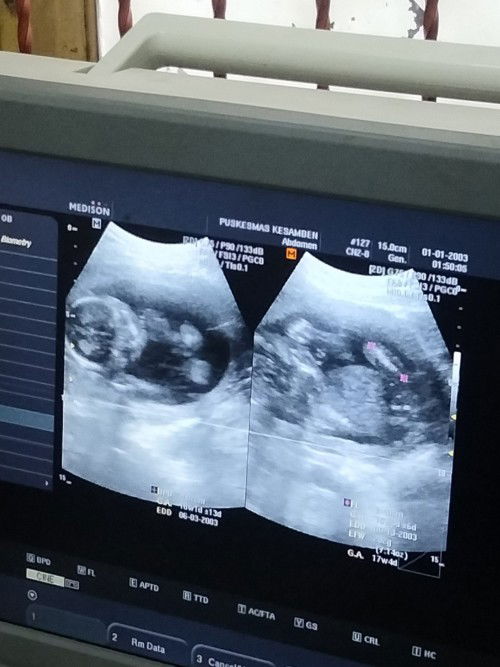

Bun ada gak yang disini usia kehamilan kemarin lalu 23w3d bbj udah 676grm, dan sekarang usia kehamilan 23w6d merasakan ngilu di bagian miss v ,, apa kira kira gedean ya bund bbj nya segitu , soalnya pas dipuskesmas gak begitu dijelasin kebeasaran atau enggaknya #seriusnanya #seriusnanya #seriusnanya